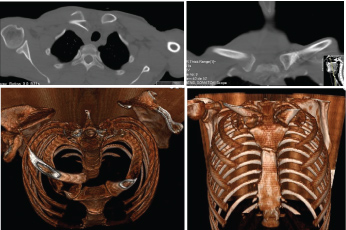

Two cerclages sutures with Ethibond® around the plate and fracture were performed to reinforce the construct. Adequate stability and hemostasis were achieved, and the wound was closed in layers. The reduction and stability of the fracture were confirmed at the end of the procedure with X-ray image intensifier (See Figure 3A and Figure 3B).

Figure 3: A and B) Immediate postop X-rays; C) 12 weeks control X-ray. View Figure 3

The patient was immobilized with a sling reinforced with a thoracic band. Passive wrist and elbow range of motion and pendulum exercises of the shoulder were allowed. Staples were retrieved fifteen days after surgery. Follow-up was performed on the 2nd week, 4th week, 3rd and 6th months after surgery. Passive range of motion of the shoulder was allowed after the first month, and active motion exercises were progressively introduced. Six months after surgery the control X-ray showed a completely united fracture (See Figure 3C). No functional pain or local tenderness at the fracture site was noticed and almost full range of motion of the right shoulder was restored on the latest follow-up. The Disabilities of the Arm, Shoulder, and Hand (DASH) score was performed at final follow-up with a value of 11.7. No major or minor complications were registered.